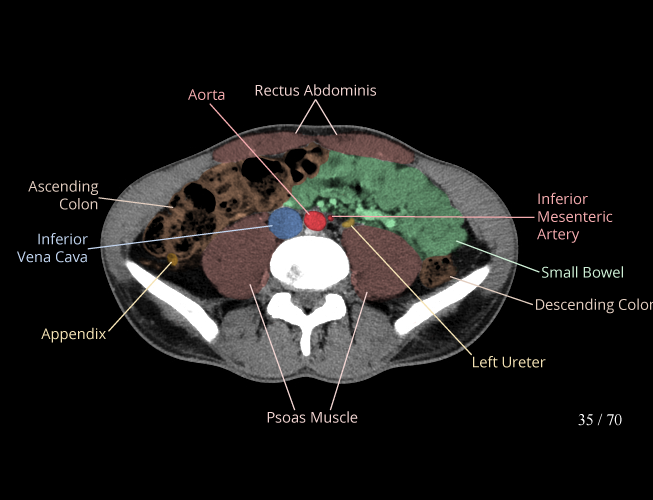

Body

Covers abdominal CT anatomy.